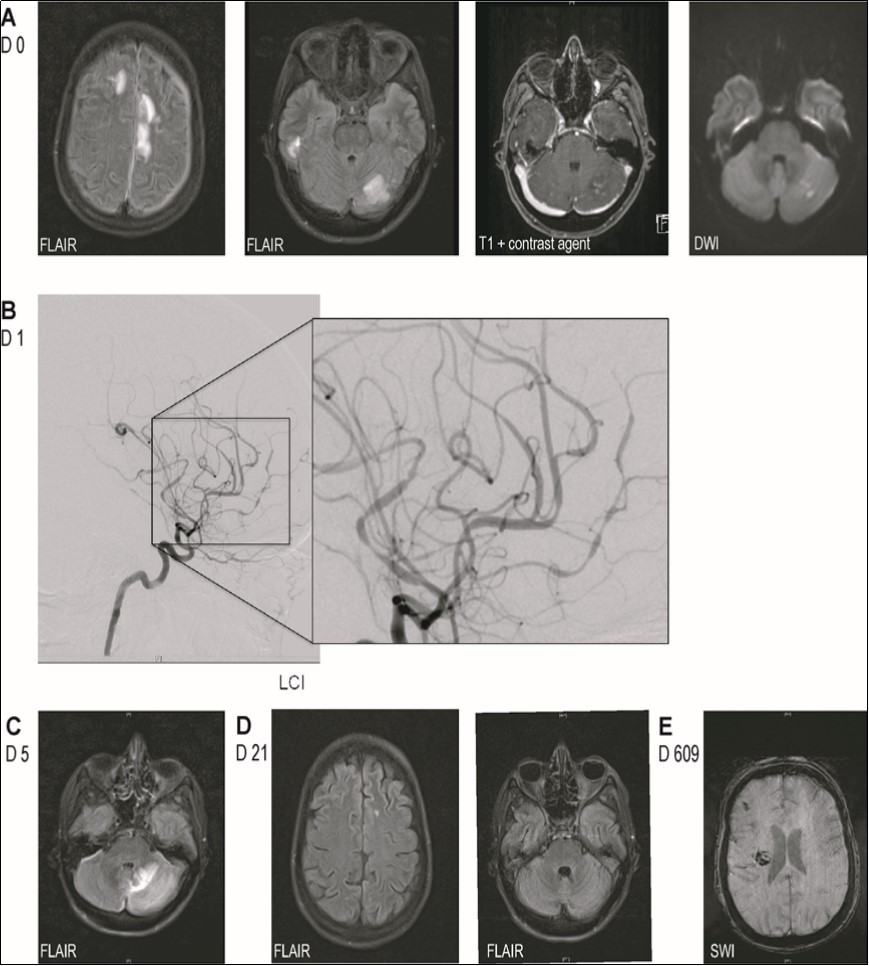

Cerebral MRI revealed multiple supra- and infratentorial FLAIR-hyperintense lesions involving both cortex and white matter. A cerebellar lesion was partially hyperintense on DWI, though without concomitant hypointensity on ADC, and showed weak contrast enhancement (Figure 1A). MR- and digital subtraction angiography displayed segmental narrowing and dilation of proximal as well as distal vessels in all territories (Figure 1C). Analysis of CSF showed normal cell count (3 cells/µl) while cytological examination revealed presence of activated lymphocytes. Glucose and lactic acid levels were normal, protein level was elevated (168mg/dl) and there was intrathecal IgM- and IgG-synthesis. Infectious causes were ruled out (including panbacterial and panfungal PCR, QuantiFERON-TB Gold in Tube Test©, CMV, EBV, enterovirus, HIV, FSME, VZV, hepatitis B/C, cryptococcus neoformans, candida and aspergillus species, borrelia burgdorferi, treponema pallidum). We diagnosed cerebral vasculitis and due to the patient's rapid decline directly administered a methylprednisolone pulse followed by an oral tapering with prednisolone without performing a biopsy. Four days after the start of steroid-therapy basal ganglia hemorrhage caused left-sided hemiplegia and anarthria. By that time, MRI showed progression of the aforementioned FLAIR-hyperintense lesions (Figure 1C) without any contrast enhancement along with new cerebellar microbleeds and bilateral narrow subdural hygroma (after lumbar puncture). On MRA intracranial artery changes had resolved. We intensified immunosuppression by administration of cyclophosphamide.

Figure 1.Imaging findings. (A) MRI-images on admission showing multiple supra- and infratentorial FLAIR-hyperintense lesions involving both cortex and white matter and one cerebellar lesion with weak contrast enhancement and partial DWI-hyperintensity. (B) Digital subtraction angiography showing segmental narrowing and dilation of proximal as well as distal vessels in all territories. (C) MRI-images 4 days after start of steroid-therapy showing progression of the FLAIR-hyperintense lesion. (D) MRI images after administration of methylprednisolone and cyclophosphamide showing nearly full regression of parenchymal lesions. (E) MRI shortly before the patient's death showing blood degradation products in the right frontal subarachnoid space and right basal ganglia.

Owing to the uncommon clinical presentation of cerebral vasculitis we screened for antineuronal-autoantibodies. Anti-DPPX-antibodies were detected in CSF and serum (both 1:100, cell-based indirect immunofluorescence assay) establishing the additional diagnosis of anti-DPPX-encephalitis. Whole body FDG-PET/CT did not suggest underlying malignancy. After cyclophosphamide and plasmapheresis the FLAIR-hyperintense lesions on MRI disappeared almost completely and MRA still showed normalization of intracranial arteries (Figure 1D). Anti-DPPX-titer dropped to 1:32. Hyperekplexia and myoclonus decreased under symptomatic treatment with clonazepame. Therapy with rituximab was started. After two months she was transferred to a rehabilitation unit from where she returned three weeks later somnolent, tetraplegic and anarthric. EEG revealed non-convulsive status epilepticus that was successfully terminated by valproate, also leading to some clinical improvement. However, as anti-DPPX-titer had risen to 1:1000 we initiated a second plasmapheresis-cycle. Thereafter anti-DPPX-titer dropped to 1:100. Another cycle of rituximab and treatment with azathioprine were started. Five weeks later she was again transferred to the rehabilitation unit, where she improved markedly, being able to use a wheelchair independently, walk over short distances in a gait training device, use her right arm and ingest food orally.

21 months after initial contact, the patient was admitted to our hospital's internal medicine unit because of an acute renal failure with urosepsis requiring hemodialysis. In addition cardiac cirrhosis with ascites was diagnosed. In the neurological examination the patient was somnolent, showed a spastic, left-sided hemiparesis and a newly increase of myclonus. Cerebral MRI displayed blood degradation products in the right frontal subarachnoid space, a new microbleed in the left temporal white matter as well as whole brain atrophy (Figure 1E). Anti-DPPX-titer had risen to 1:32000. In the further course, the patient developed aspiration pneumonia eventually causing septic shock with multiple organ failure that lead to her death at the age of 34. An autopsy was not performed (Figure 2).